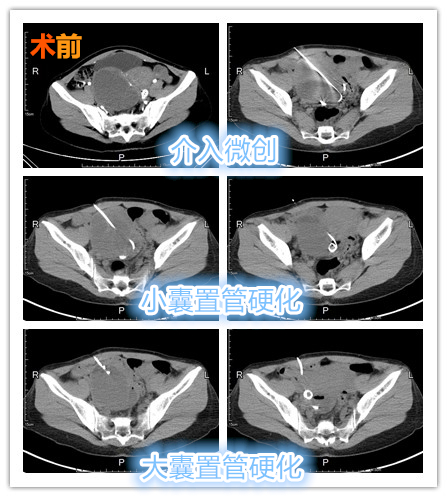

CT引导下的巧克力囊肿硬化治疗是如何进行的?

CT引导下治疗,选择合适、安全的经皮肤途径,利用金属细针准确穿刺到“巧囊”内,引入并留置引流管,将囊液充分引流,并反复冲洗直至清亮后,最后使用聚桂醇泡沫硬化剂保留囊腔内持续硬化治疗。因有保留引流管,可重复上述操作治疗,直至确认囊壁较为彻底坏死后,再将引流管拔除结束治疗。虽较超声引导下治疗时间长,但可彻底硬化治疗囊壁,尤其适合单发较大囊肿(>5cm),有生育要求且未婚患者。巧克力囊肿与CT介入硬化治疗的那些事

【一针双囊】巧治巨大分隔型巧克力囊肿

中年女性患者,发现巨大巧克力囊肿3年余,近期腹痛、腹胀感有所加重。术前CT提示巨大巧囊内出现分隔,术中先穿刺较小分隔囊腔,置管引流管冲洗硬化治疗,后续置管较大分隔囊腔留置引流管术后持续冲洗硬化治疗,达到一次穿刺治疗双囊腔效果。

一针双囊

介入微创守护女性健康!